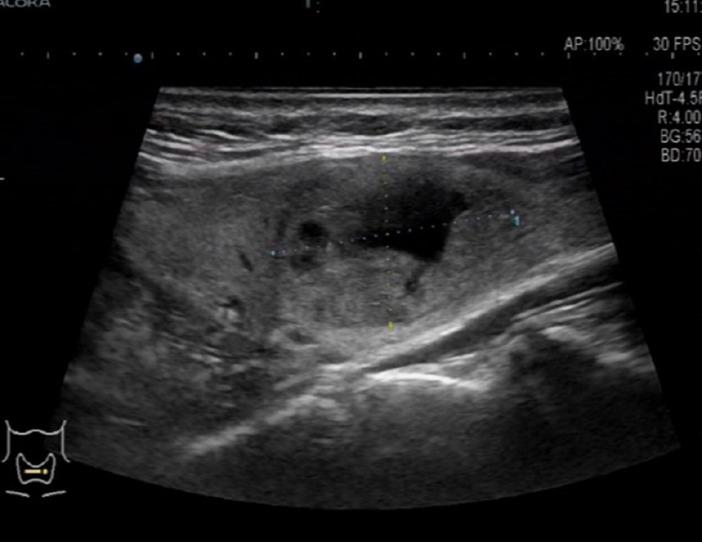

We report a rare case of fibrocystic osteitis associated with a parathyroid adenoma, which was discovered by chance due to a rib tumor. Abnormally elevated serum parathyroid hormone and calcium ion were found before surgery. We suspected primary hyperparathyroidism, and color Doppler ultrasound suggested the presence of a thyroid mass. With informed consent by the patient and her family, we first removed the rib tumor, and one week later, resection of the parathyroid adenoma and thyroid mass was performed on both sides, and the patient recovered well after surgery.

我们报告1例与甲状旁腺腺瘤相关的纤维囊性骨炎罕见病例,该病例因肋骨肿瘤偶然发现。术前发现血清甲状旁腺激素和钙离子异常升高。我们怀疑为原发性甲状旁腺功能亢进,彩色多普勒超声提示甲状腺有肿物。在患者及其家属知情同意后,我们首先切除肋骨肿瘤,1周后双侧切除甲状旁腺腺瘤及甲状腺肿物,术后患者恢复良好。